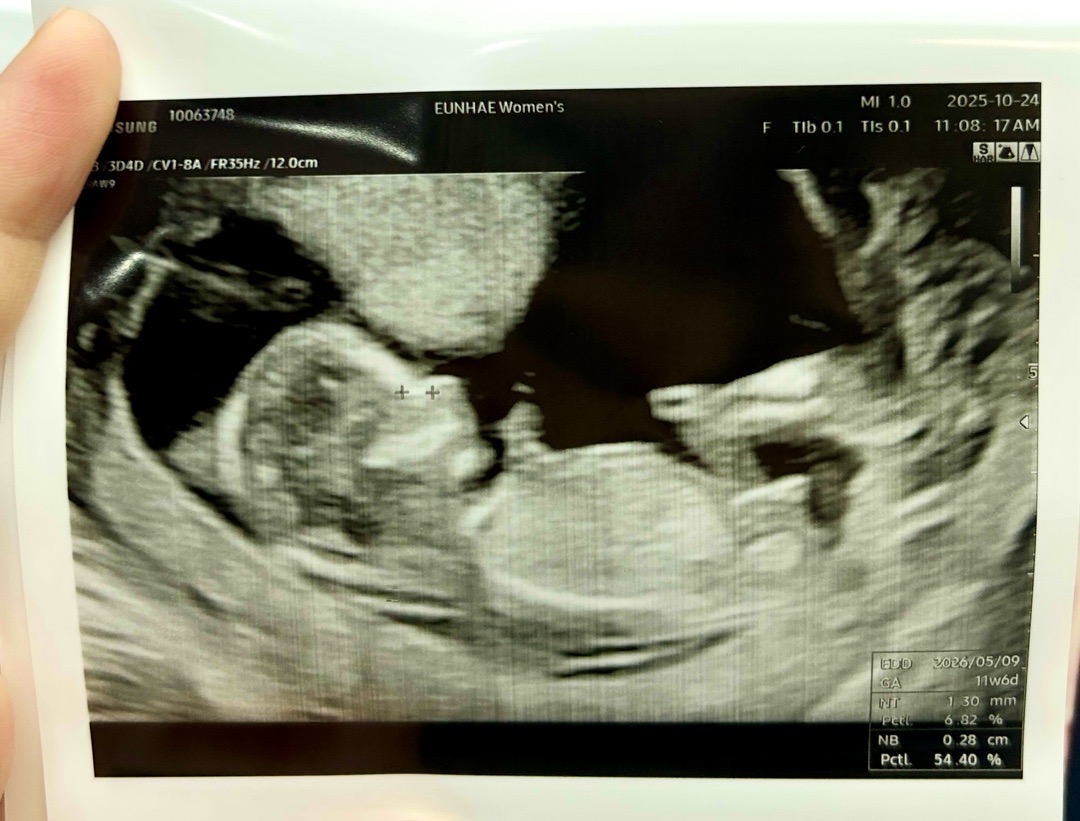

12주차 초음파 성별 각도법 봐주세요💓